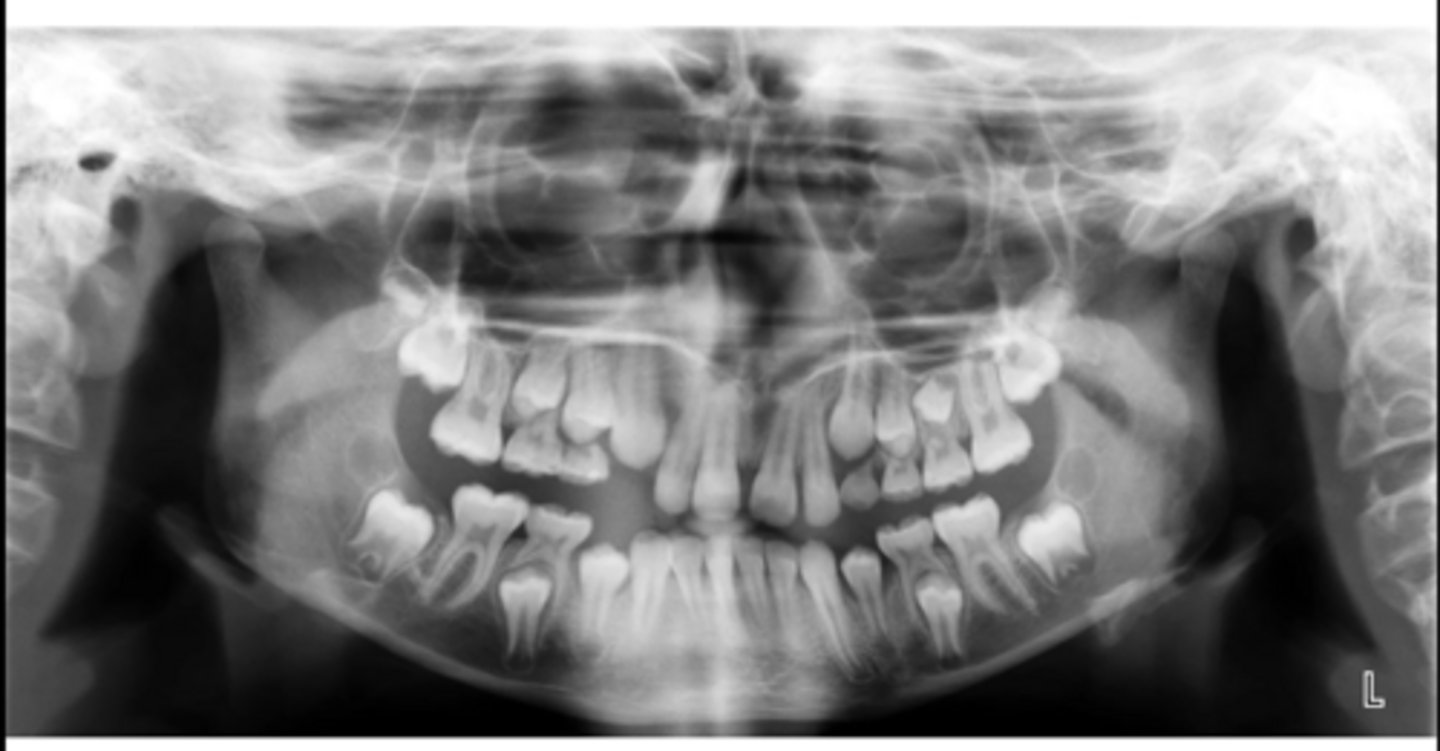

Premolar #13 (unerupted in pano) is more tilted than the opposing side (#4), which indicates an ectopic eruption pattern.

(Primary teeth w/o resorbing roots is also present)

What abnormalities/concerns do you see in this pano?

Third molars and mandibular right second premolar

Are there any congenitally missing teeth in the maxillary arch?

#29 (mandibular right second premolar)

Are there any congenitally missing teeth in the mandibular arch?

mandibular right second molar

Are there any retained primary teeth?

maxillary canines

Are there any impacted teeth?